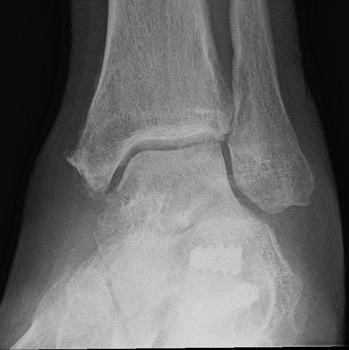

Stage 3 Tibialis posterior dysfunction / Rigid flatfoot

Options

Double (subtalar / TNJ) versus triple arthrodesis (subtalar / TNJ / CCJ)

- 23 feet with stage 3 T posterior dysfunction

- treated with double v triple arthrodesis

- no difference in outcomes

- shorter operative time with double arthrodesis

Burrus et al J Foot Ankle Surg 2016

- 16 rigid pes planus comparing double and triple arthrodesis

- increased nonunion and worse functional outcomes with double arthrodesis

Triple Arthrodesis